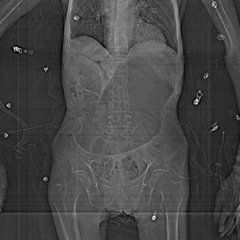

診斷:腹部手術後2~3天或大量進餐後出現上腹部膨脹、頻繁大量的嘔吐,或從胃管吸出大量胃液,即應考慮有胃急性擴張的可能。立位X線腹部平片可發現充滿氣體和液體的擴張胃腔,有巨大的胃內液平面,嚴重者胃腔可達盆腔內。吞服少量鋇劑可以勾畫出擴大的胃輪廓,鋇劑在胃內排空延緩甚至完全瀦留,有時十二指腸水平有受壓表現。

1.X線檢查腹部立體透視或平片,可見一個大的胃泡,並有一寬大的氣液平面,胃陰影明顯擴大,嚴重者可占據腹腔大部分,胃大彎可達盆腔內。給小量鋇劑可迅速降至胃的最低處,而發現擴大的胃輪廓。胃排空遲緩甚至完全瀦留。因胃擴大而使左橫膈上升。部分病人同時有小腸麻痹。如果合併胃壁壞死或穿孔,膈下有積氣及積氣征。

2.腹部B超檢查可見胃高度擴張,胃壁變薄。胃內若為大量的瀦留液或食物殘渣,超聲很容易測出其量的多少和在體表的投影。嚴重時胃邊界可達整個上腹部,下緣可超過臍下。若胃內為大量氣體,其界限不易與腸脹氣區分。